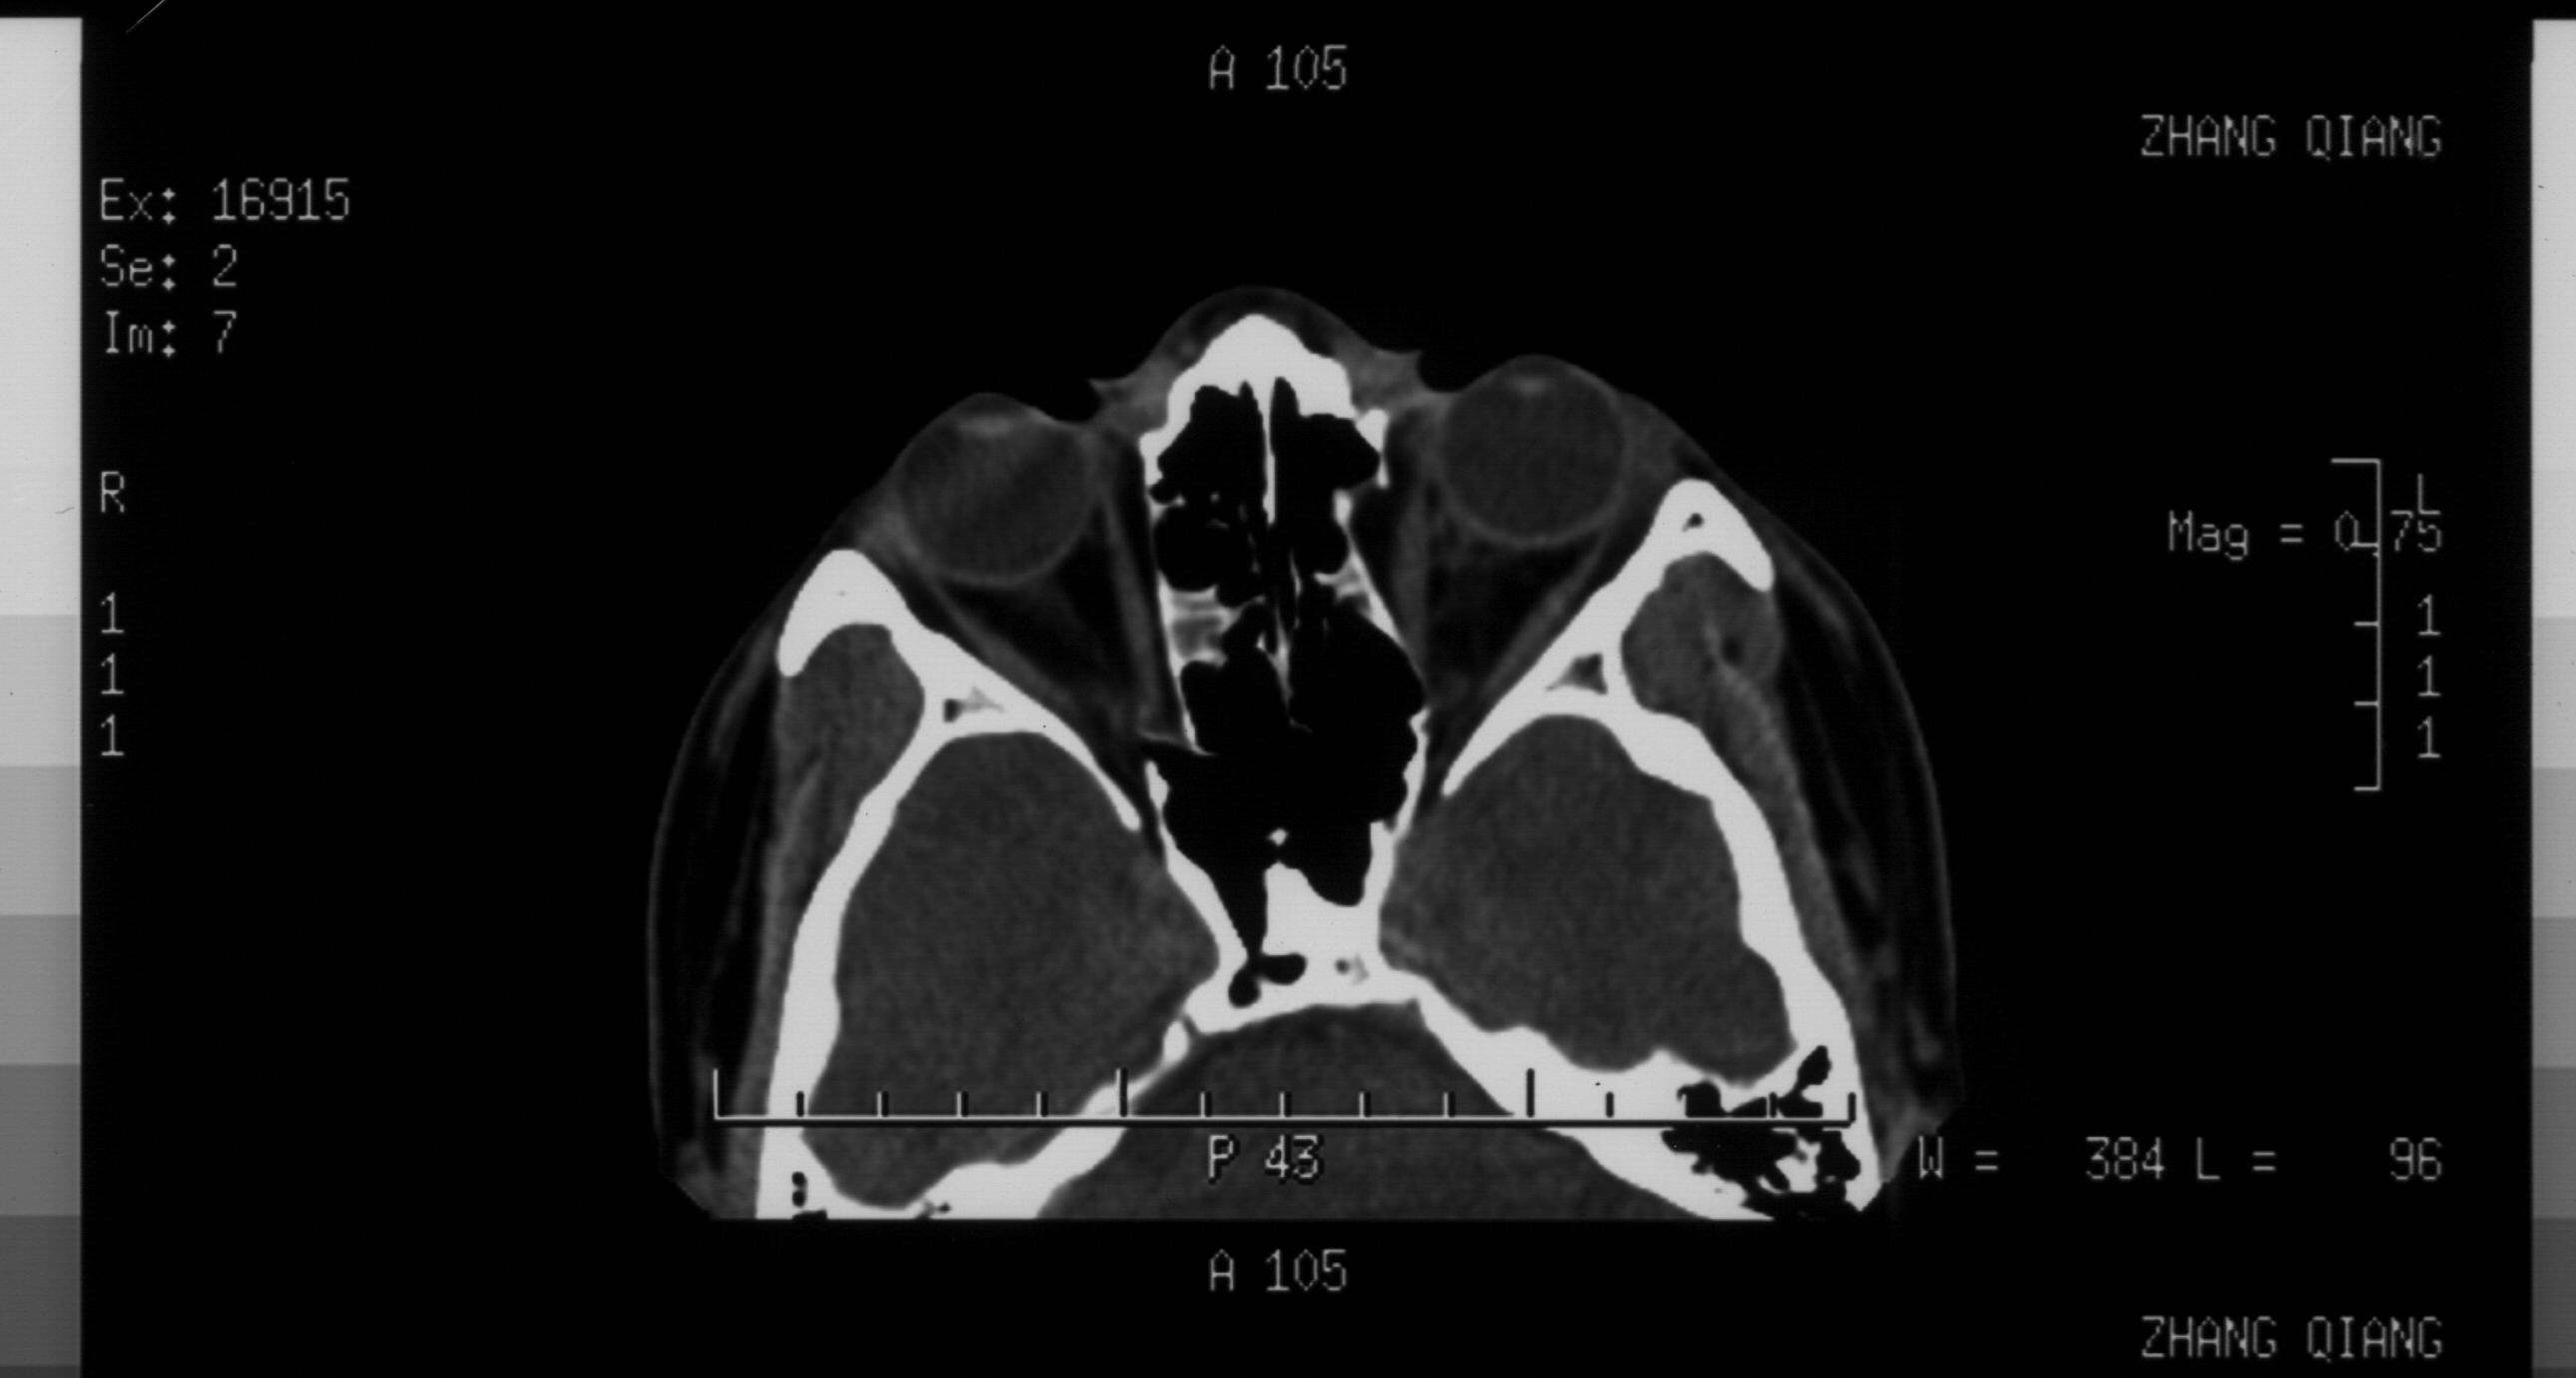

双眼拳击伤 双眼全方位复视 请解读一下ct片 如何治疗 谢谢

你好! 关于你的CT片的质量问题,也许不能、马上解决,不过请以后再选片时,注意以下三个问题:1、外伤患者应有至少一张包括视神经层面。2、尽量标明TOPO定位像3、请对关键层面给出软组织窗。就目前情况,我们确实有猜 的成分。好了,言归正传。

你的CT片分析结果,至少有两点是可以确定的。1、双侧眼眶内侧鼻多发骨折 2、鼻骨骨折。 |